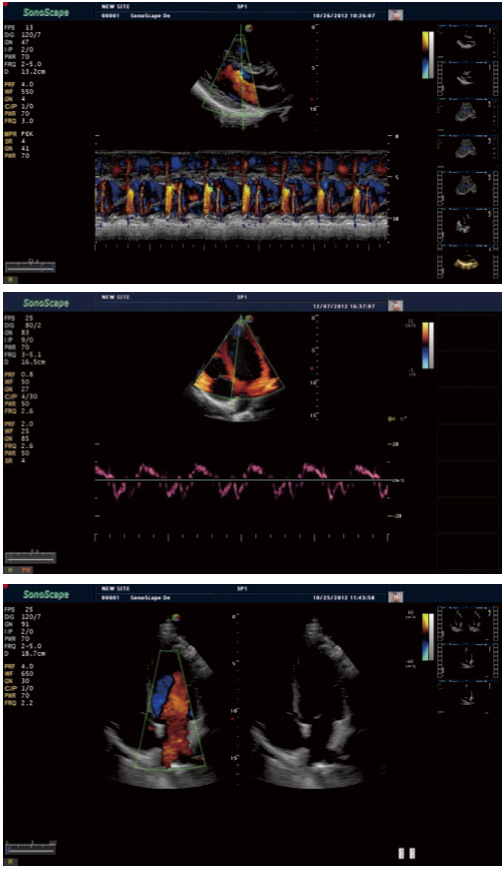

Sistema S40 es una excelente solución a las necesidades de imagen cardiaca clínica , lo que proporciona el rendimiento de imagen robusta y versatilidad necesaria a través de una amplia gama de pacientes cardíacos. Forjado con canales físicos prolongados y tecnologías cardiacas SonoScape tales como TDI y el eco estrés , integrado con transductores cardíacos dedicados y suficientes herramientas de medición profesionales , S40 permite a los médicos para dar un diagnóstico preciso , seguro y rápido en cardiología y proporcionar a los pacientes las mejores soluciones de tratamiento .

Tissue Doppler Imaging S40 está dotado con Doppler tisular que proporciona velocidades y otra información clínica sobre las funciones de miocardio , lo que facilita los médicos clínicos para analizar y comparar los movimientos de las distintas partes del corazón del paciente .

S40 ofrece sonda de alta densidad phased array para satisfacer las necesidades tanto de alta velocidad de fotogramas y la resolución de la calidad premiun en la obtención de imágenes cardíacas . Además , ofrece la excelencia de imágenes en multiplano adulto y sonda TEE pediátrico. Gracias a la alta sensibilidad de mapeo Doppler color de SonoScape , S40 mostrarán diagnóstico cardiaco precisa más allá de su imaginación.

Modo M anatomico, con esta tecnología cardiaca avanzada que cuenta con tres cursores que se pueden ajustar en cualquier posición y el ángulo de forma simultánea, S40 ofrece el mejor enfoque para reducir el tiempo que el paciente -por- tiempo que se mantiene la precisión de diagnóstico , además de las funciones cardíacas normales , adquiriendo toda la información , incluso en situaciones de difícil exploración de difícil posicionamiento corazón.

Eco estrés es la combinación de la ecocardiografía 2D con un estrés físico o farmacológico , que puede determinar la forma en los músculos del corazón responden al estrés y se utiliza principalmente para diagnosticar y evaluar la enfermedad de la arteria coronaria . S40 estrés paquete de eco con totalmente integrado y una interfaz de fácil programación puede personalizar a sus necesidades y todas las características ayudar a entregar flujo de trabajo optimizado para la puntuación movimiento de la pared y la presentación de informes.